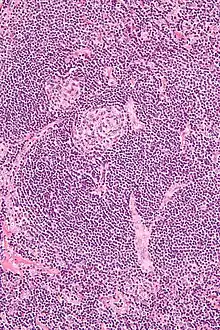

Micrograph of Castleman disease showing hyaline vascular features including atrophic germinal center, expanded mantle zone, and a radially penetrating sclerotic blood vessel ("lollipop" sign). H&E stain.

• Hyaline vascular: regressed germinal centers, follicular dendritic cell prominence or dysplasia, hypervascularity in interfollicular regions, sclerotic vessels, prominent mantle zones with an "onion-skin" appearance.[14]